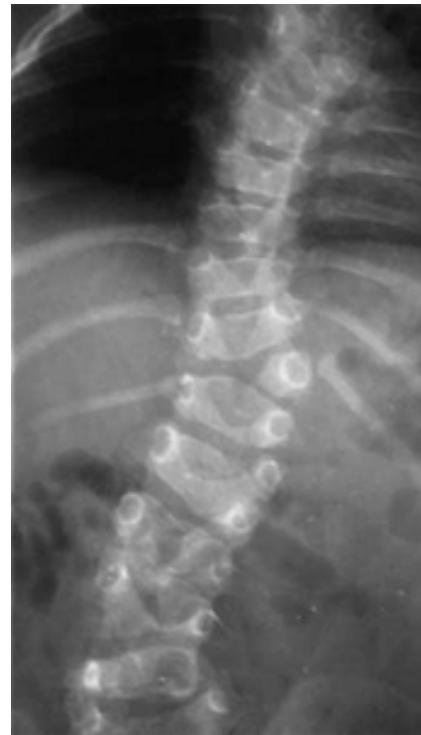

Osteoporotic Vertebral Compression Fracture

- Commonest vertebral injury

- Etiology: Minor trauma in osteoporotic people

- Prevalence: Affects up to 50% of people over 80 years old

- Diagnosis: Lateral radiographs

- Initial treatment: Observation and pain management

- Kyphoplasty: Reserved for patients with recalcitrant symptoms after 4-6 weeks of nonoperative treatment